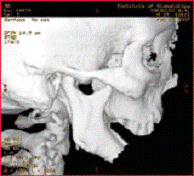

СК томограмма пациента с дефектом

нижней челюсти после огнестрельного ранения (а), моделирование замещения

дефекта аутотрансплантатом из малоберцовой кости по данным СКТ (б)